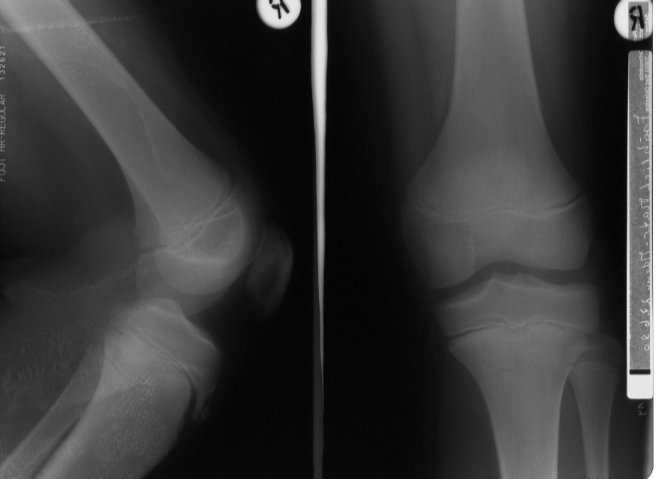

Morbus Osgood Schlatter

Bei dem Morbus Schlatter handelt es sich um eine Erkrankung, welche bei Jugendlichen im Alter zwischen 14 bis 16 Jahren abläuft. Es handelt sich um eine Verknöcherungsstörung des Ansatzbereiches der Kniescheibensehne am Schienbeinkopf. Der Ansatzbereich der Sehne verwächst nicht mit dem Schienbein, so daß hier ein isolierter Knochenkern bestehen bleibt.

Dies führt zu einer Verdickung, welche bei stärkerer sportlicher Belastung und insbesondere beim Knien schmerzhaft sein kann.

Die Diagnose wird gestellt durch den typischen lokalen Untersuchungsbefund und ein Röntgenbild.